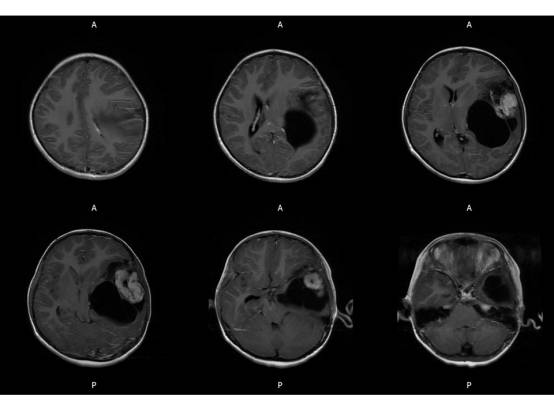

MR平扫及增强示:

MR

左侧颞叶见大块状等长T1等长T2异常信号,FLAIR呈高新,DWI(b=1000)实质部分呈稍高信号,ADC实质部分呈等信号,边界尚清,周围脑实质受压。注入GD-DTPA后病变实质部分呈明显强化。